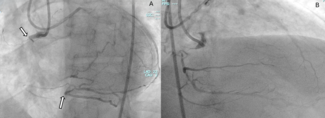

Video Supplement: Potential Alternative Mechanism of HydroDynamic Contrast Recanalization in Complete Total Occlusion Seen on DeepOCT+NIRS Imaging

Video Supplement to "Potential Alternative Mechanism of HydroDynamic Contrast Recanalization in Complete Total Occlusion Seen on DeepOCT+NIRS Imaging" (Clinical Image).

Video. Deep optical computed tomography recording of the right coronary artery after crossing the chronic total occlusion using the HydroDynamic contrast recanalization (HDR) technique. The video shows the potential mechanism of HDR, demonstrating contrast circumferentially inside the plaque and circumferential intimal dissection after balloon angioplasty of the lesion.